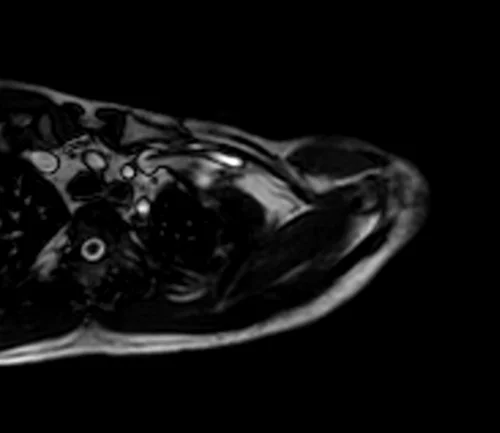

mra upper arm loc 4 - MRI